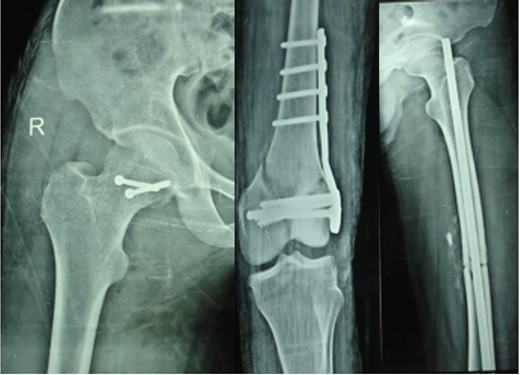

Blood parameters were within normal limits. X-ray of the pelvis revealed a right posterior hip dislocation with Pipkins's type II fracture (Rt) and ipsilateral distal medial condylar fracture with a fracture shaft of femur (Lt) (Figs 1 and 2). A CT scan confirmed the infrafoveal right-sided Pipkin's-II fracture of the femoral head (Fig. 3). A nerve conduction velocity study of lower limb suggested neuropraxia of sciatic nerve. Following attempt of closed reduction, CT scan and X-rays revealed incongruous reduction.

Initial X-ray: left thigh (anteroposterior view) and right knee (oblique view).